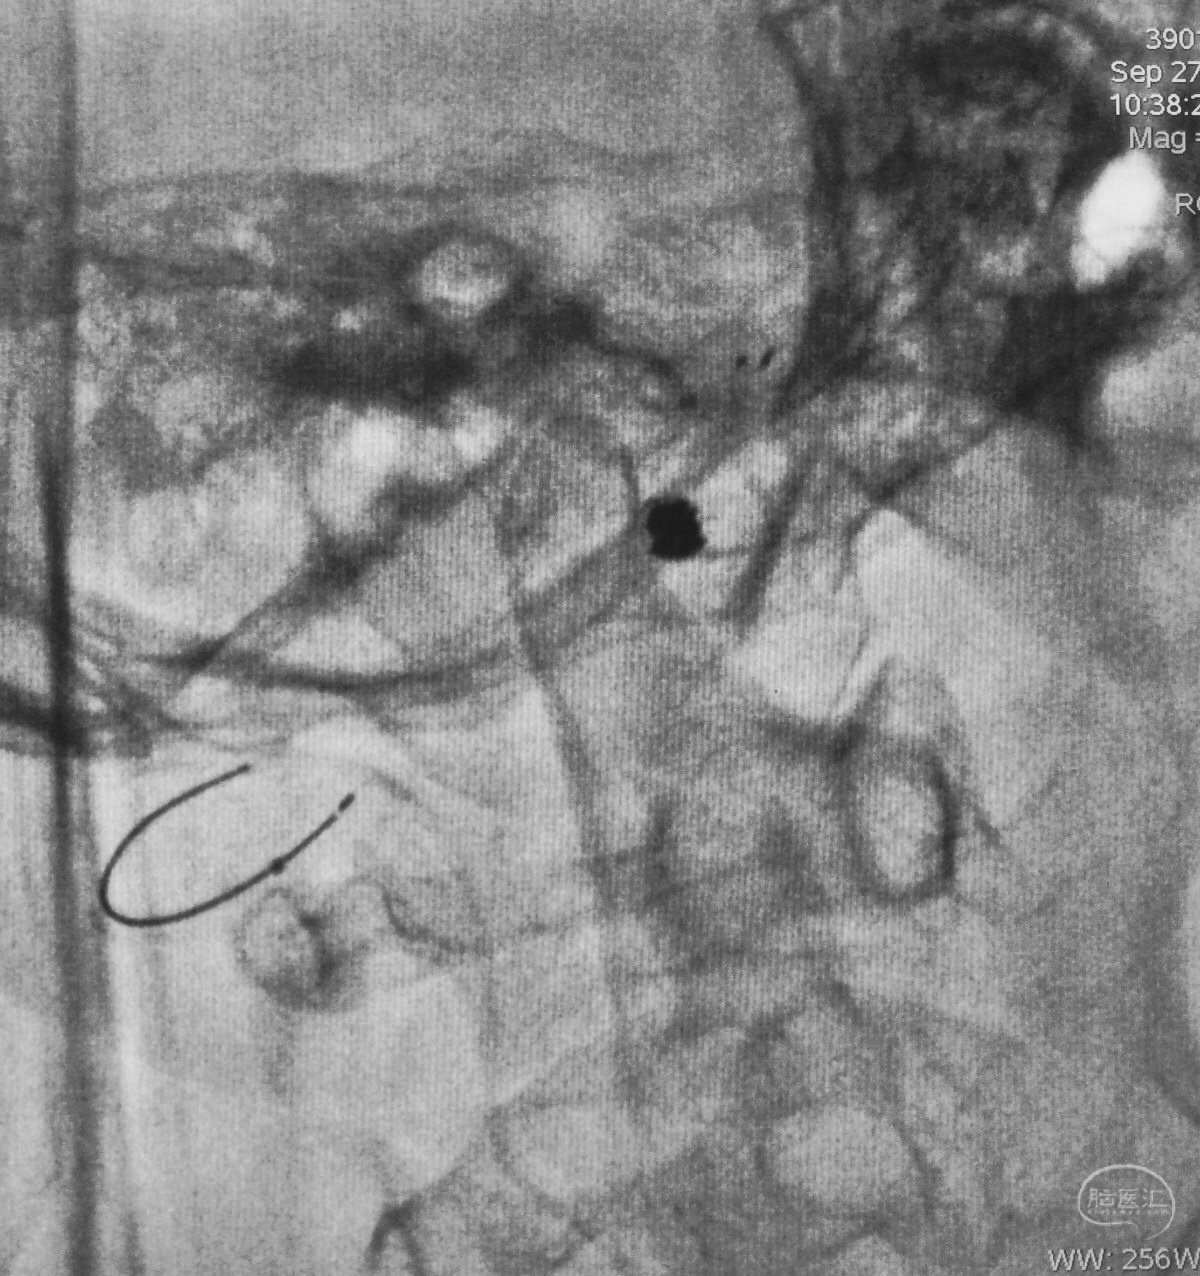

Echelon 10微导管头无论塑成C形还是S形,均无法稳定于动脉瘤腔内,遂使用回马枪技术,使微导管成襻通过,管头折返入瘤腔。

跨瘤颈释放Solitaire 4×20支架(蓝线),压住微导管(红线),在支架保护下经返折的微导管送入弹簧圈填塞瘤腔。

依次送入QC-2-4-3D,2-3-Helix,1.5-2-Helix,1.5-2-Helix四枚弹簧圈,最后一枚弹簧圈将管头(箭头)顶出瘤腔。